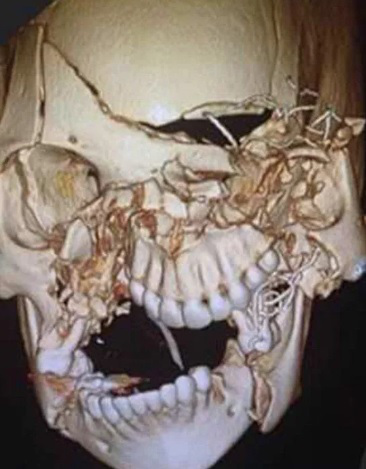

Η φωτογραφία που βλέπετε απεικονίζει το «πριν» και το «μετά» της εκτενούς αναδόμησης κρανίου στην οποία υποβλήθηκε μια γυναίκα, που φέρεται να ενεπλάκη σε τροχαίο ατύχημα.

Η εικόνα του διαλυμένου κρανίου της, όπως φαίνεται στις εικόνες που δημοσίευσε ένας εκ των χειρουργών της κάνει το γύρο του διαδικτύου για λόγους καθαρά εκπαιδευτικούς μήπως και με κάποιο τρόπο ευαισθητοποιηθούν συνειδήσεις

Δεν είναι γνωστό το τι ακριβώς συνέβη πριν η άτυχη γυναίκα φτάσει στο νοσοκομείο, αλλά κρίνοντας από τις φωτογραφίες, πρέπει να ήταν πολύ σοβαρό τροχαίο δυστύχημα.

Υπάρχουν αναφορές ότι πρόκειται περί γυναίκας που εμπλέκεται σε αυτοκινητιστικό ατύχημα και δεν φορούσε ζώνη ασφαλείας.

Όπως βλέπετε, δεν είναι μόνο η άνω και κάτω γνάθος που έχει διαλυθεί, αλλά το κρανίο έχει σπάσει και θρυμματιστεί σε διάφορα σημεία, με τα κομμάτια του απλώς να… επιπλέουν. Έχουν τοποθετηθεί σχεδόν παντού λάμες.

Ο επίσημος… κατάλογος των τραυματισμών της περιλάμβανε:

Τραυματική εγκεφαλική βλάβη με ενδοκρανιακή αιμορραγία

Τραυματικό των ματιών με εκτενές πρήξιμο

Εκτεταμένα κατάγματα προσώπου (άνω και κάτω γνάθος, ζυγωματικά κ.α.)

Εικόνα 1: Το «πριν»